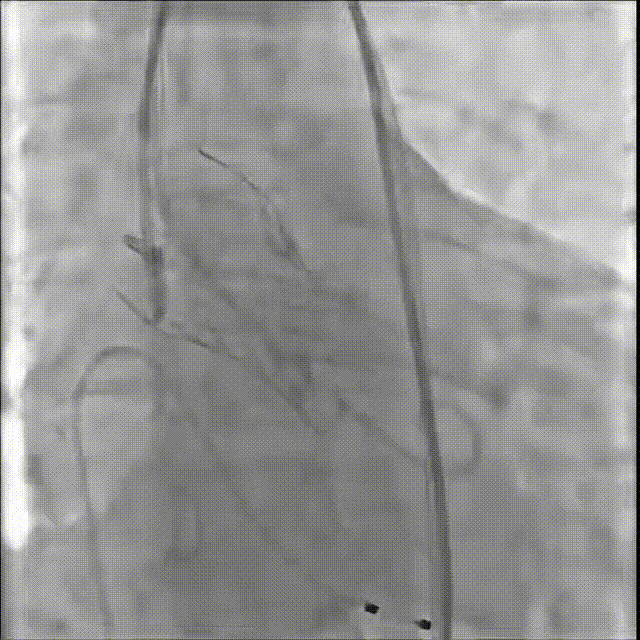

修建成教授 南方医科大学南方医院(点击查看专家详细简历) 细微之处防未然,创新携手寸寸安: 愈知临床无小事,任何风险的蛛丝马迹,都可能牵动全局。我常对团队说,真正的严谨,是将所有潜在 scenario 视作必然,在术前便一一拆解、化解 —— 如同在堤坝溃决前便筑牢每一寸基石,让风险连萌芽的机会都没有。 此次应用全球首创的预装干瓣,是基于对患者的综合考量,拥抱创新,实践创新,让创新携手助力“万全之策”的重要环节。 术前推演需要结合器械的特性:深度了解才能得心应手,结合患者基础病的相互影响并落实到术后 72 小时的并发症预警,每个环节都要像精密齿轮般咬合无误。这份 “穷尽万一” 的准备,从来不是对完美的苛求,看似耗时费力,实则是对生命最质朴的承诺 ——以医者的周全,携手创新的产品,为患者的万无一失不断努力! 患者病史 因 "反复胸闷伴活动后呼吸困难 3 年" 入院:患者 3 年前无明显诱因反复出现胸闷,部位在前胸,有憋气感,间有心悸,伴有活动后呼吸困难;外院就诊,查心脏彩超示 "主动脉狭窄、二尖瓣关闭不全"; 既往有高血压 20 余年,长期服用氨氯地平阿托伐他汀钙片降压治疗;有糖尿病 1 年,长期服用二甲双胍、阿卡波糖降糖治疗。 术前超声提示:主动脉瓣增厚、钙化并狭窄(重度)及关闭不全(轻度) 术前超声提示:主动脉瓣增厚、钙化并狭窄(重度)及关闭不全(轻度) 术前CT Type1型(R-N)二叶瓣,中度钙化集中在左窦瓣叶边缘及右无交界处,主动脉根部直径21.6mm,LVOT直径22.2mm,瓣上限制逐渐增大;双侧冠脉开口高度可,瓣叶短,窦部宽度足够,双冠VTC空间>4mm,预估冠脉风险小。 左室腔小,室间隔膜部短,有一定PPI风险;外周双侧入路无明显迂曲,双侧髂外动脉存在散在钙化、股动脉直径大,右股低分叉,能够支持20F大鞘通过。 手术策略 推荐右侧股动脉为主入路,放置20F大鞘,左侧为辅助入路,常规穿刺;使用20球囊预扩,预装AV23瓣膜;左右重叠位:RAO 1° CAU 28° ;右窦居中位:LAO 22° CAU 0° ;左冠切线回调:LAO 35° CRA 17° ;心室小,术前术中积极补液调整容量,做好循环崩溃处理准备。 手术过程 主动脉根部造影 20mm球囊预扩 - 无腰无漏 瓣膜初始定位 工作位观察瓣膜 - 冠脉通畅,位置合适 最终造影观察 - 无瓣周漏、挂钩处于最右方-Commisural Alignment 术前压差120mmHg,术后压差2mmHg。 Prostyle A®预装干瓣——助力临床最优化解决方案: 平衡的径向支撑力:该病例为TYPE 1型二叶瓣,对产品的径向支撑力是一种考验,术后影像彰显Prostyle A®综合设计带来平衡的径向支撑力,轻松应对高钙化病变,符合中国国情,为二叶瓣患者带来信心保障; 轻松过弓,精准可控:该病例主动脉弓角度可,但弓距小,考验产品的通过性能,术中顺利过弓,未使用snare轻松过弓; 预装干瓣 便捷顺安:金仕生物专利抗钙化技术运用纳米技术去除组织内的细胞碎片和磷脂,封闭游离醛基,从根本上阻断了瓣膜钙化的多项因素,显著提升了瓣膜的耐久性;同时,相比较传统戊二醛保存方式,干式存储最大限度的保留心包的亲水亲油平衡,还原组织天然曲柔性,进一步保障了瓣叶开合,保证长期耐久性。